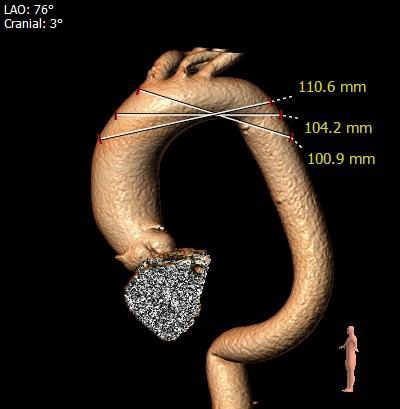

主动脉根部评估

根部概览

瓣上分析&心室大小分析

• 三叶式主动脉瓣,轻度钙化,钙化主要分布在右无交界,敞口型流出道,人工瓣膜锚定难度高,存在向上或向下位移风险,采用右窦中心体位,瓣环下2-4mm进行初始释放;

• 左、右冠状动脉开口高度可,结合STJ及瓦氏窦内径,冠脉堵塞风险小,术中造影关注冠脉灌注情况;

• 根据根部及瓣上分析,该患者钙化不重,瓣口较大,采取不预扩,直接植入TaurusElite AV31型号瓣膜策略,瓣膜释放后观察形态,必要时采用25mm球囊进行后扩;